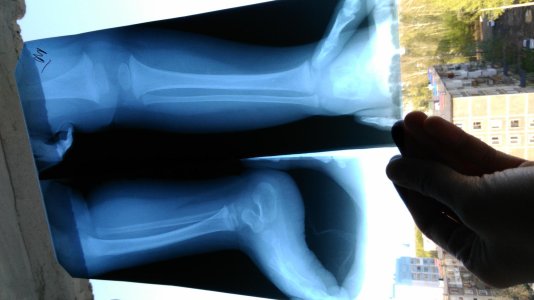

Здравствуйте! Ребёнок,1 год 2 месяца, разогнался и неудачно присел, не мог после этого наступать на правую ногу. На снимке хирург увидел трещину в голеностопе, наложили лангетку,сказали не давать опираться на ногу пока носим её,наложили на 10 дней. Когда разрешается опираться на ногу,подскажите пожалуйста.хирург наш ничего не сказал,сейчас ушёл в отпуск,другого хирурга в городе нет...

Наши снимки

Вложения

• IMG_20160506_080422.jpg

IMG_20160506_080422.jpg

172,4 КБ · Просмотры: 440

• IMG_20160506_080541.jpg

IMG_20160506_080541.jpg

165,3 КБ · Просмотры: 414